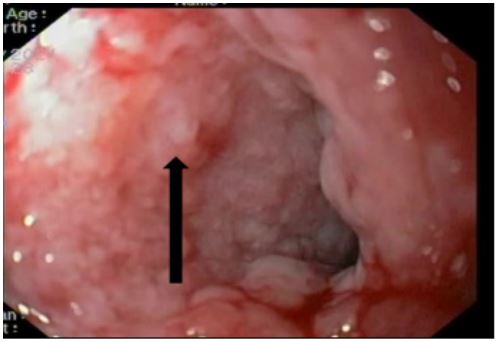

A 31-year-old female patient with a Bochdalek hernia with complete stomach migration into the left pleural space and ischaemia. Intraoperatively, after bringing down the stomach, the proximal half was found to be gangrenous with perforation. Upper partial gastrectomy and esophagogastric anastomosis were performed. The surviving stomach was oedematous and ischemic, but not gangrenous. A CT scan with intravenous contrast 48 hours later revealed a severely ischemic stomach, raising concerns about its viability. A recheck laparotomy to test the stomach remnant revealed considerable edoema but looked viable. The anastomotic site looks healthy. On the 12th postoperative day, an oral contrast study revealed a frank leak from the anastomosis, with the infected collection tracking up to the left perinephric space, with endoscopy confirming the results (Figure 6). At this point, management options were limited. The covered stent and reoperation were deemed risky. Endoscopic Vacuum (E-VAC) therapy was considered a safe choice in these conditions.

A UGI endoscopy performed to prepare for the endovac revealed a partial breakdown of the anastomosis with a defect size of 3 cm and a subdiaphragmatic cavity filled with slough. The cavity was entered with a scope, and de-sloughing was accomplished with a brush. Normal saline was used to irrigate the cavity. Endovac was used. Forty-eight hours after beginning endovac therapy, there was a significant decrease in SIRS response as measured by fever, pulse rate, WBC count, and CRP. Endovac was done twice more at 5-day intervals. The therapy lasted two weeks in total. At each endoscopic session, the size of the sponge used was reduced, and the cavity size and amount of slough were significantly improved (Figure 7). After 2 weeks of endovac therapy, a CT oral contrast study revealed a significant reduction in cavity size with a well-formed fistula that closed in about 8 weeks. Endoscopies were performed at 3 and 6 months. Both were normal, and the patient is currently on a complete oral diet.

Figure 6: Post operative anastamotic site leak in stomach and placement of E Vac sponge.

Figure 7: Healed anastamotic leak of stomach after E vac therapy.